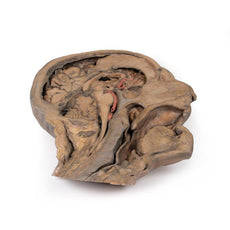

The head and neck of the specimen provides views of both superficial and deep structures in the region. The calotte has been removed ~2cm superior to the orbits to expose the brain in relation to the endocranial cavity. The transverse section through the cerebrum demonstrates the relation of the grey matter cortex to the white matter medulla, as well as the lateral ventricles with a small amount of choroid plexus visible in the base of both spaces. The skin and superficial fascia on the right side has been retained and false-coloured to display the angiosomes of the face and posterior neck. On the left side, the superficial tissues have been dissected to expose the muscles of facial expression, muscles of mastication, and deeper structures of the infratemporal fossa including the lingual nerve, terminal branches of the external carotid artery into the superficial temporal and maxillary arteries.

The head and neck of the specimen provides views of both superficial and deep structures in the region. The calotte has been removed ~2cm superior to the orbits to expose the brain in relation to the endocranial cavity. The transverse section through the cerebrum demonstrates the relation of the grey matter cortex to the white matter medulla, as well as the lateral ventricles with a small amount of choroid plexus visible in the base of both spaces. The skin and superficial fascia on the right side has been retained and false-coloured to display the angiosomes of the face and posterior neck. On the left side, the superficial tissues have been dissected to expose the muscles of facial expression, muscles of mastication, and deeper structures of the infratemporal fossa including the lingual nerve, terminal branches of the external carotid artery into the superficial temporal and maxillary arteries.